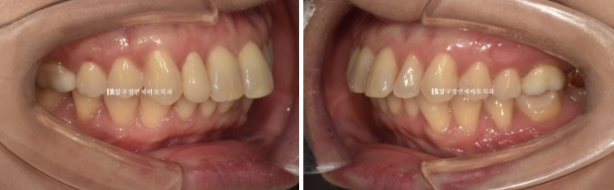

치료 전 후 보겠습니다.

좌 - 치료 전 / 우 - 치료 후

24.02~24.12

앞니 배열 개선과 가위교합 개선

쓰러진 큰 어금니는 잘 세웠습니다.

치간삭제를 통한 아래 앞니 배열의 개선

과개교합과 중심선의 개선